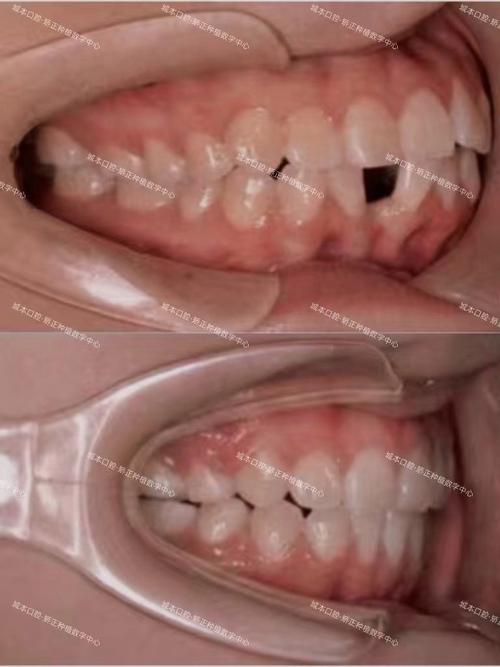

典型案例:

一位因牙列拥挤导致上门牙唇倾10°的牙性嘴突患者,通过拔除4颗第一前磨牙,固定矫正器内收前牙6个月后,上门牙唇倾角度恢复正常(105°),嘴唇回收约4mm,侧面观鼻唇角(鼻子与嘴唇的夹角)从90°改善至100°(正常范围为95°-100°),面部协调性显著提升。